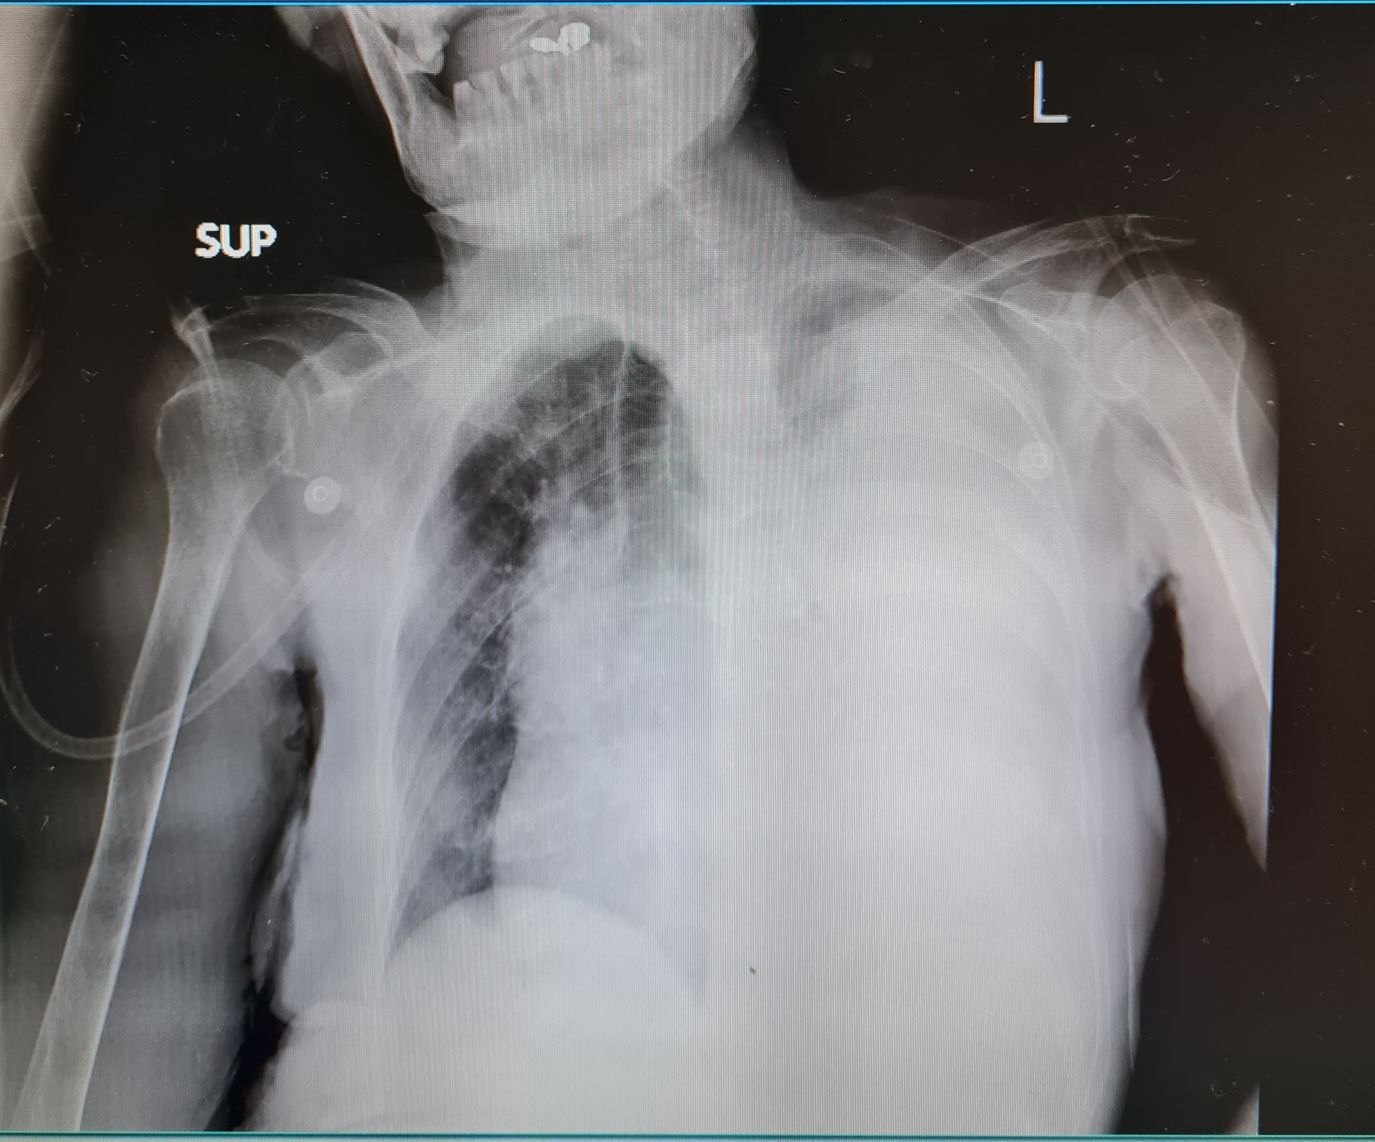

Huge pleural effusion

Large pleural effusion / empyema; leading to subtotal lung collapse and tracheal / mediastinal shift

Pleuraleffusion

Lungcollapse

Mediastinalshift